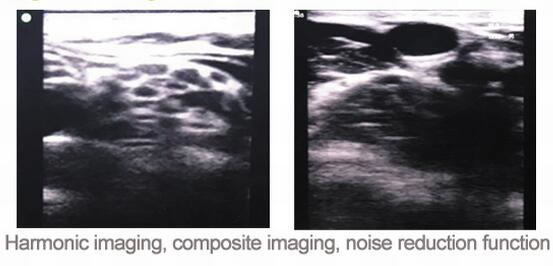

新推出C5Plus高清晰图像128阵元64通道笔记本彩超价格超低,新版本无线探头加上谐波成像复合成像和降噪处理图像可达到便携彩超水平,带屏无线探头也将首次亮相,USB探头和超声+心电+电脑一体机也优惠大促销。